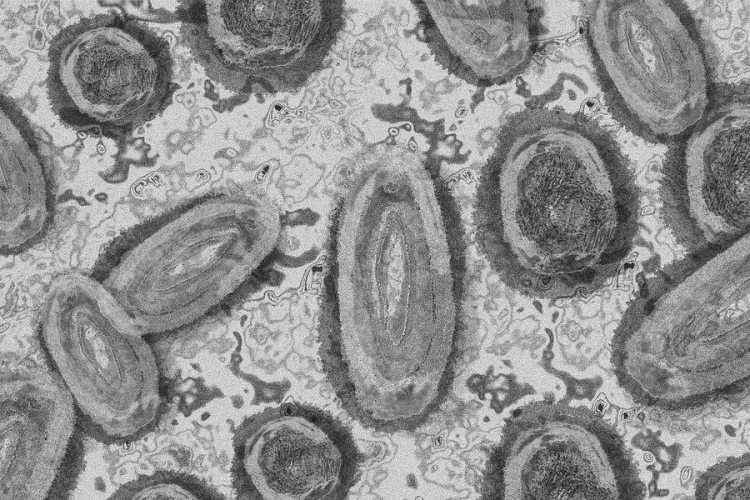

Tovább nőtt a majomhimlő-fertőzöttek száma Magyarországon

Újabb kilenc, 23-50 éves férfinél igazolták a majomhimlő-fertőzést Magyarországon, ezzel 42-re nőtt a fertőzöttek száma - közölte a Nemzeti Népegészségügyi Központ (NNK) csütörtökön az MTI-vel.

Tovább nőtt a majomhimlő magyar fertőzöttjeinek száma

Újabb hat embernél diagnosztizálták a majomhimlő vírusát, így harmincra emelkedett az igazolt fertőzöttek száma Magyarországon - közölte a Nemzeti Népegészségügyi Központ (NNK) pénteken az MTI-vel.

Újabb hét magyarnál igazolták a majomhimlőt

Újabb hét embernél igazolták a majomhimlőfertőzést a Nemzeti Népegészségügyi Központ (NNK) veszélyes kórokozókkal foglalkozó laboratóriumában; ezzel 19-re nőtt az igazolt majomhimlő fertőzöttek száma Magyarországon